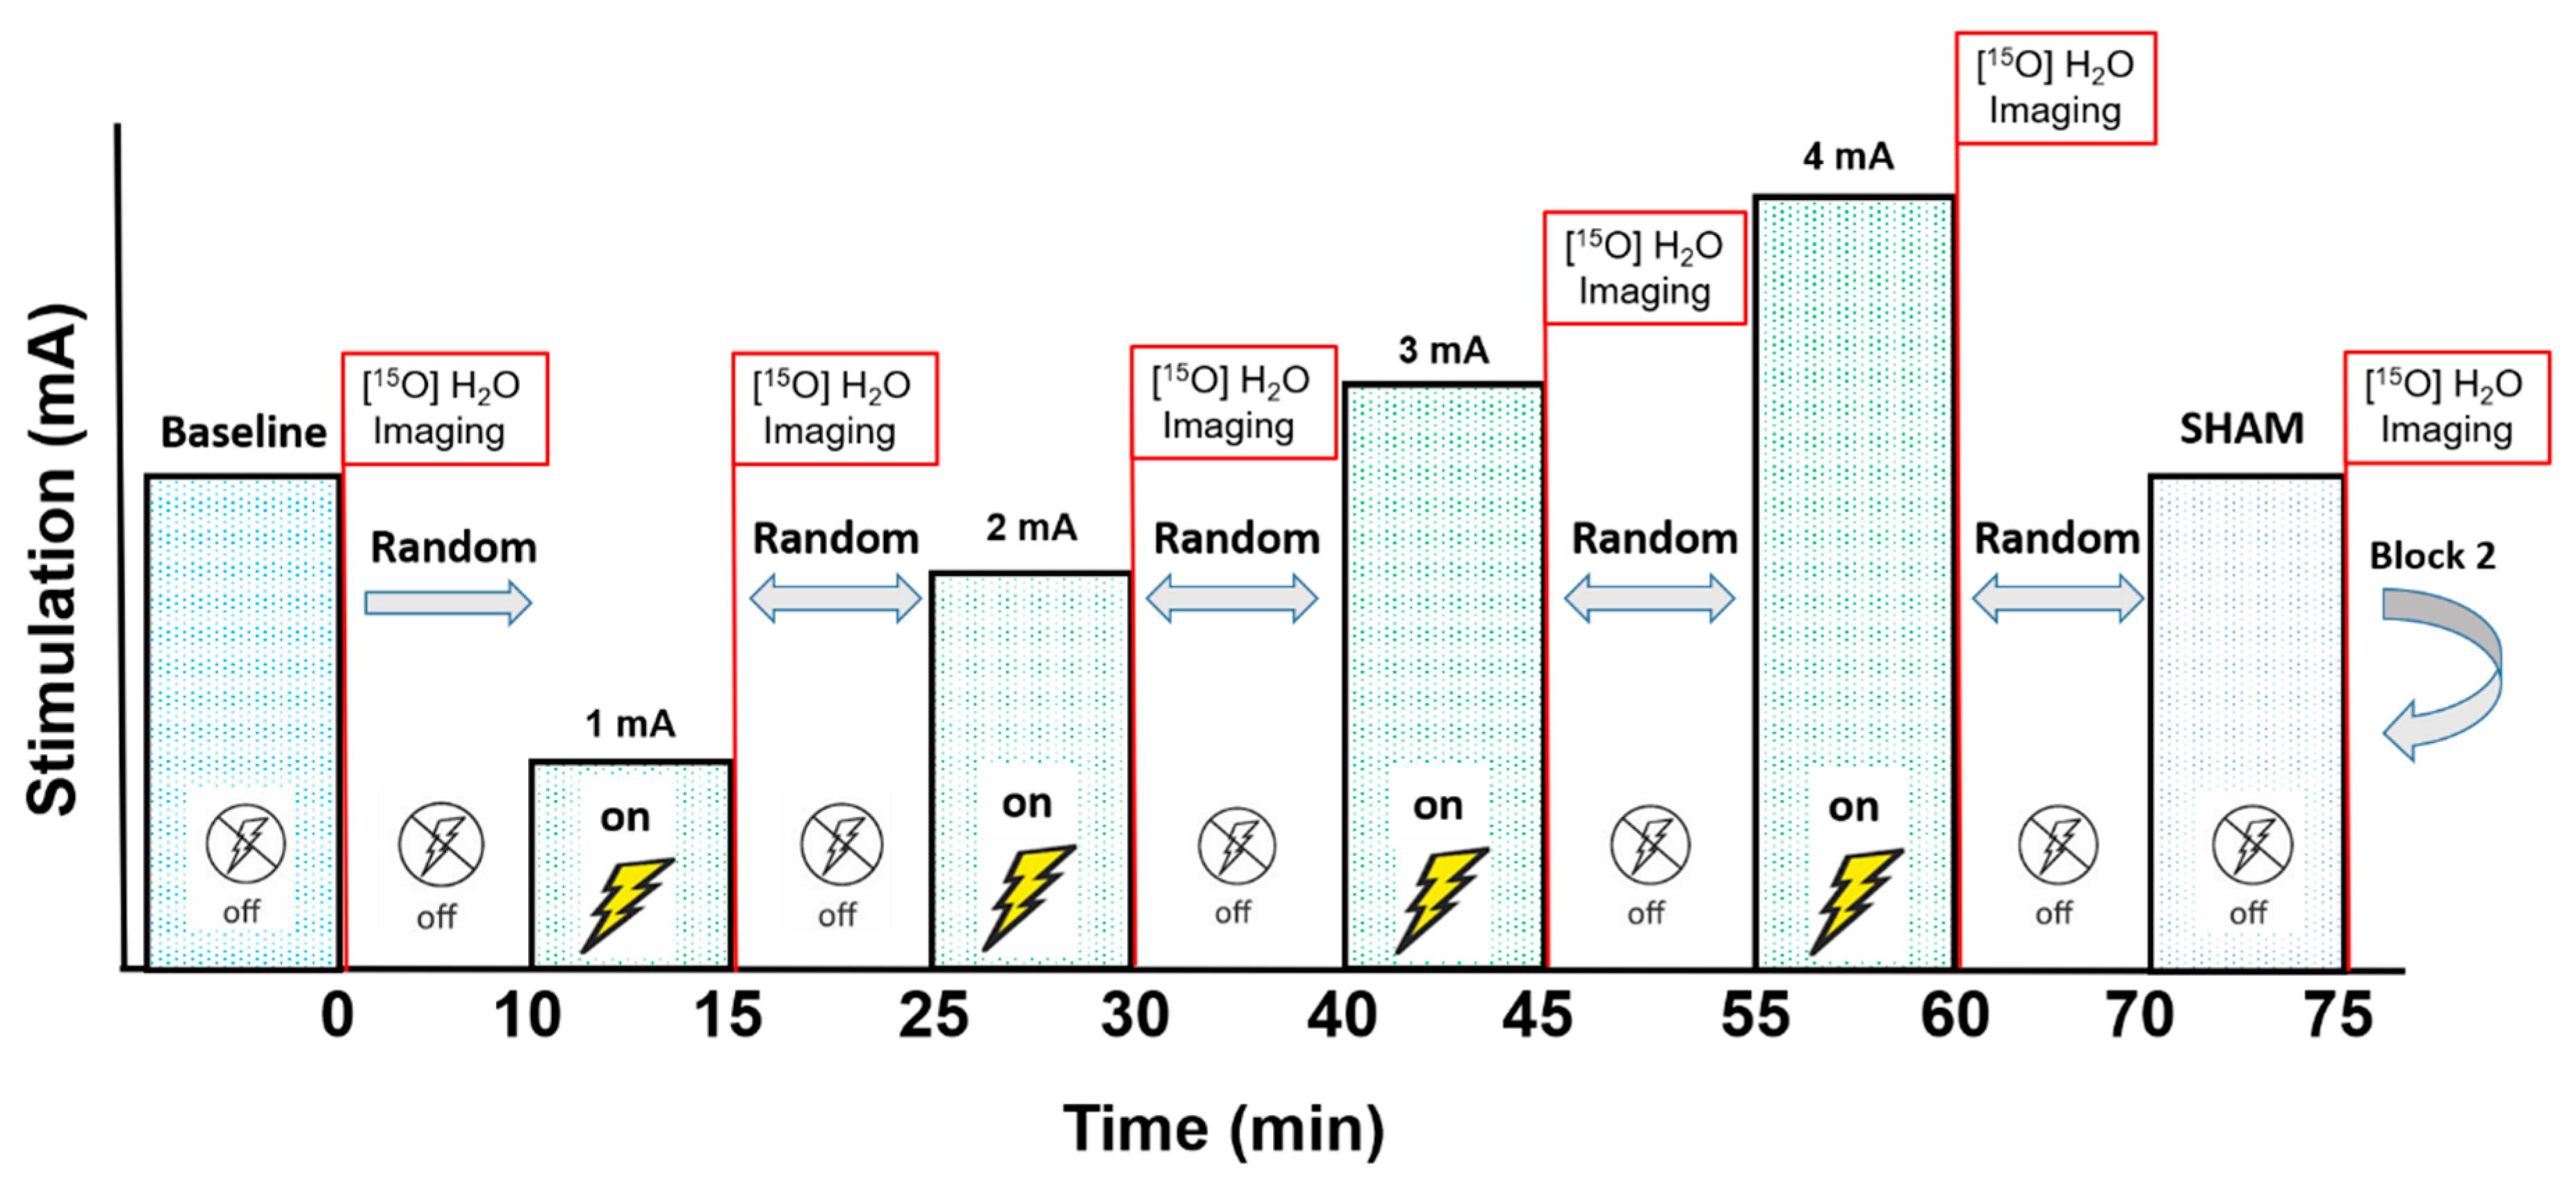

2. Materials and Methods

3.1. Experiment 1, Dorsolateral Prefrontal Cortex

3.2. Experiment 2, Primary Motor Cortex